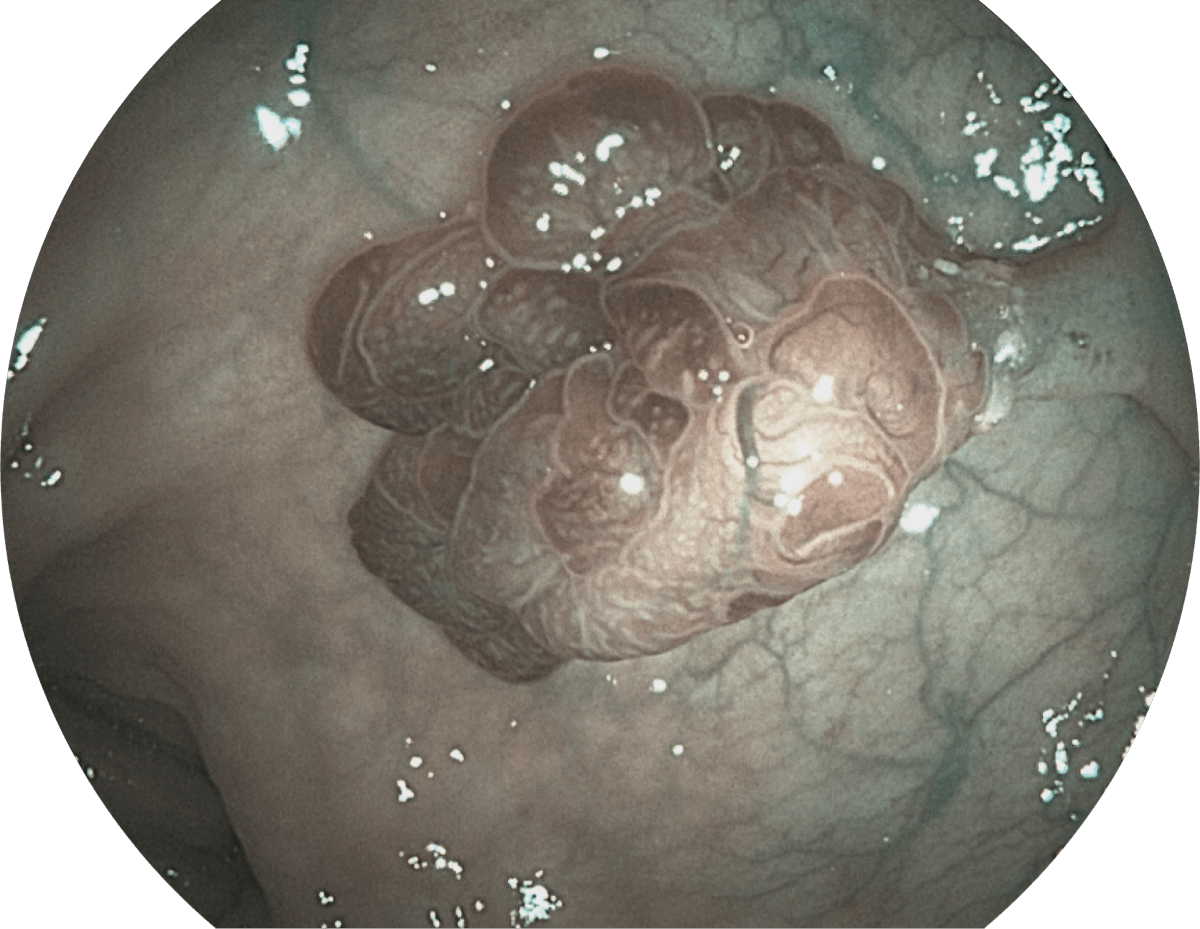

具有聚谱成像技术(SFI)及光电复合染色成像技术(VIST),可完美呈现粘膜细节及病变特征。

SFI

VIST